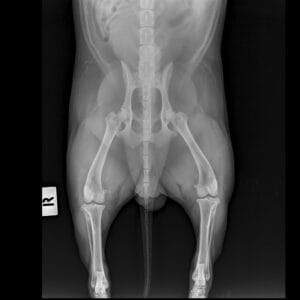

Imaging performed with digital x-rays allow us to see an animal’s body clearly without invasive procedures. The images are available almost instantly, allowing us to make faster decisions about treatment. With these images, we are able to diagnose conditions of the heart and lungs, gastrointestinal obstruction, tumors of the internal organs or bones, fluid in the chest or abdominal cavity, urinary stones or gallstones, reproductive diseases, and bone/joint disorders. For most patients, gentle restraint can be used for these procedures, however, in some cases, sedation may be necessary.